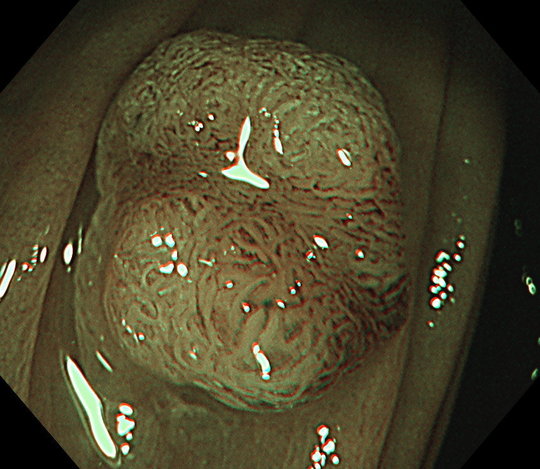

さらに桐山クリニックでは、病変発見時に、約80倍まで拡大観察することが可能な拡大内視鏡を標準使用しています。この内視鏡を使用することで、病変が腫瘍であるかどうか、切除が必要かどうか、何度も検査をすることなく、ボタン1つで評価することができます。

NBI拡大観察

病変が見つかったときには、NBI(Narrow Band Imaging:狭帯域光観察)という画像強調技術を駆使し、そのポリープが腫瘍であるかどうか、内視鏡で切除すべきか、手術などが必要かどうかなど精密検査も同時に行うことができます。

NBI診断や拡大機能を使用した内視鏡診断は高度な技術と豊富な経験が必要です。大学病院や総合病院でも十分に検査ができる医師が少ないところもありますが、当院では国立がんセンター中央病院での豊富な検査や診断経験に基づき精度の高い検査を行っています。